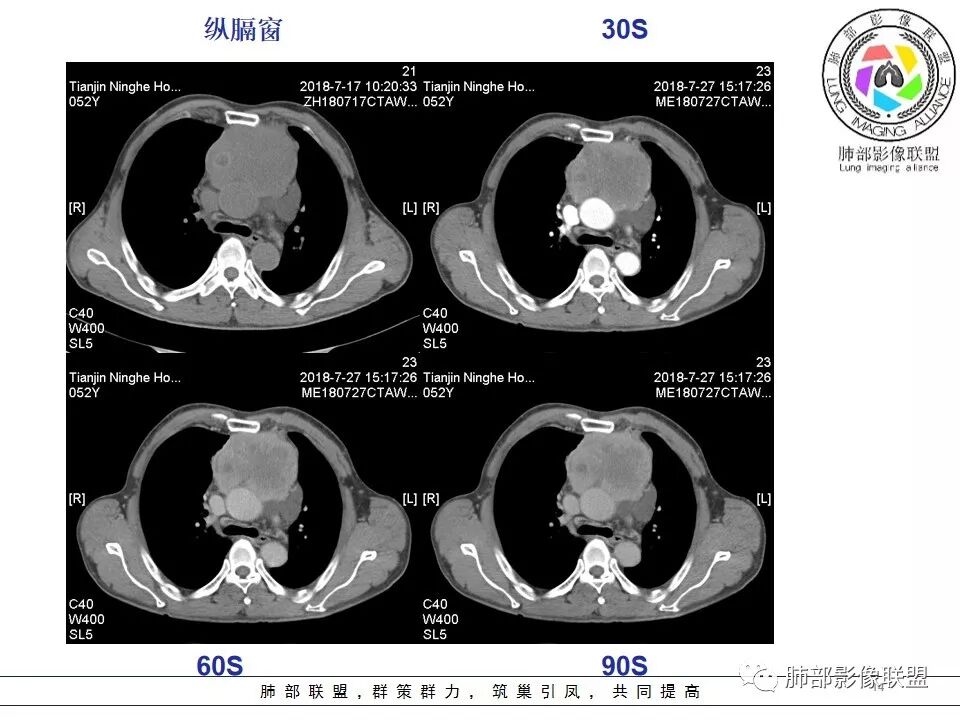

南边:强化就不用说了

大肿块,边缘不清,伴随肿大淋巴结,上腔静脉受侵犯——恶性

侵袭性胸腺瘤?胸腺癌?老年,钙化、肿大淋巴结,边缘侵犯、累及心包、侵犯上腔静脉——支持

a.多数密度均匀,少见囊变坏死,见纤维分隔影及钙化---多见于低位胸腺瘤,而且纤维分隔影以AB型显著, 实质性钙化多提示AB型及以上,A型钙化多发生于被膜钙化,呈蛋壳样;

b.密度不均匀,囊变坏死多见,纤维分隔影少见,有钙化---多见于高危胸腺瘤及胸腺癌以上,尤其大片囊变坏死多见于B1型以上胸腺瘤跟胸腺癌;钙化多见于肿瘤实质内,非边缘区,多发的泥沙样、微钙化及多形性钙化多见于B2、B3型;

b. ①纵隔脂肪间隙模糊、胸膜、心包侵犯、膈肌受累--见于高危胸腺瘤及胸腺癌,但是心包侵犯多见于B3胸腺瘤跟胸腺癌

②纵隔大血管侵犯、肺转移、膈神经麻痹、淋巴结转移及远处血行转移---多见于胸腺癌,B3胸腺瘤罕见

1.  病灶内实质性钙化,提示AB型以上胸腺瘤、胸腺癌或类癌,其中微钙化往往提示高危型胸腺瘤跟胸腺癌、类癌,同时也排除了淋巴瘤(淋巴瘤不会有钙化);

2.  病灶呈分叶蔓延倾向,其内大片状囊变坏死,周围脂肪间隙模糊,提示高危型胸腺瘤或胸腺癌,但是类癌周围脂肪间隙往往很清晰;

3.  胸膜、心包侵犯,多提示高危型胸腺瘤中的B3型胸腺瘤、胸腺癌、类癌

4.  纵隔淋巴结肿大及纵隔大血管(上腔静脉)受侵犯,提示胸腺癌或类癌。

5. 此患者NSE增高,提示神经内分泌肿瘤可能,纵隔神经内分泌癌最常见的是不典型类癌,胸腺类癌临床上可伴相关临床表现。肿瘤体积巨大,边缘清晰,强化显著(与鳞癌不同),肿瘤内边缘规则的管状血管影(鳞癌内血管是破坏、纤细、僵硬);